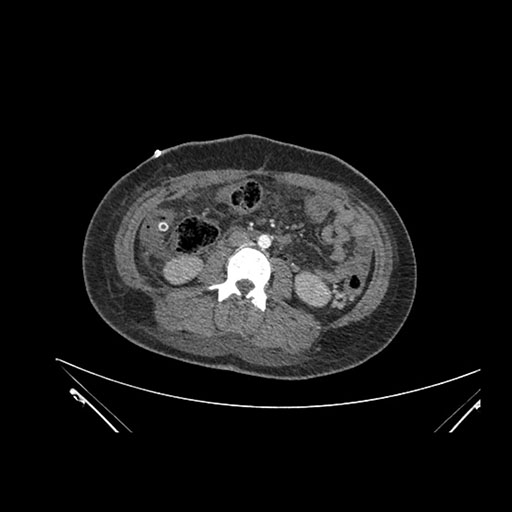

Axial Arterial

Axial Venous

Coronal Arterial

Coronal Venous

Imaging analysis

Based on initial findings, which issue(s) would you be most concerned about?